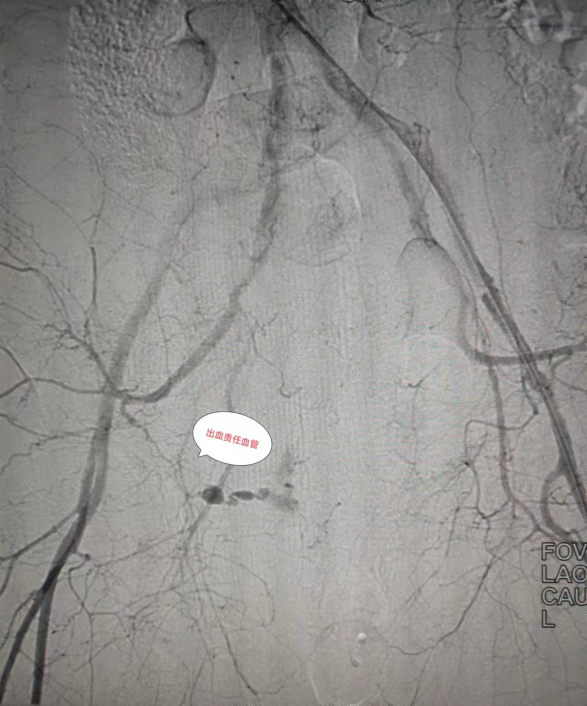

在認(rèn)真尋找出血血管

只見(jiàn)張濤主任

憑借高超技藝與熟練操作

很快便找到責(zé)任血管

精準(zhǔn)超選到出血?jiǎng)用}

給予彈簧圈

及明膠海綿栓塞治療

(圖:術(shù)中可見(jiàn)動(dòng)脈破裂出血,超選入出血?jiǎng)用}造影證實(shí))